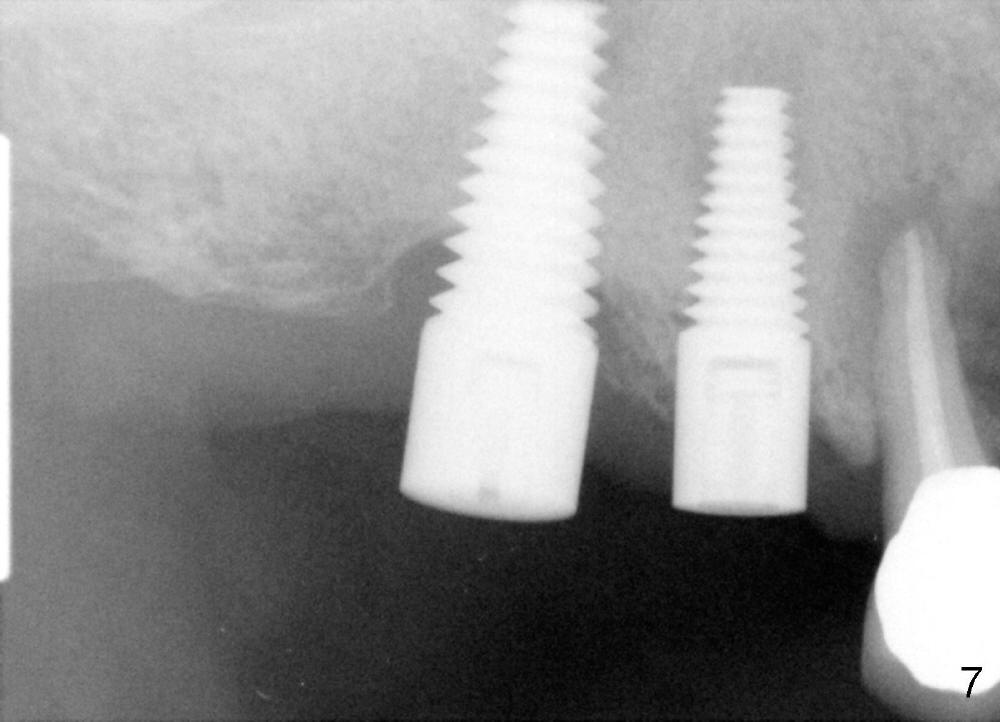

Due to finance, no treatment is provided to #5 (Fig.5 (4.5x14 mm tap),6 (4.5x14 mm implant)). PA (Fig.7) is taken 8 months postop. The crowns at the sites of #3 and 4 have been cemented for 9 months.

It appears that the crack root of #5 does not have bacteria or that there is no direct communication between #4 and 5 for bacteria to travel. The radiolucency is away from the implant site.